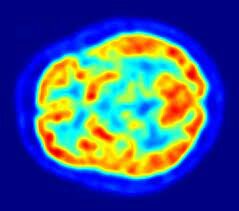

• Radiofármacos

Radiofármacos

James Robertson y sus asociados en el Laboratorio Nacional Brookhaven construyeron el primer escáner PET de un solo plano, apodado el "reductor de cabeza". [2​] Uno de los factores más importantes para la obtención de imágenes fue el desarrollo de radiofármacos. En particular, el desarrollo de 2-fluorodeoxi-D-glucosa (2FDG)